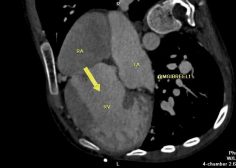

Criss-cross heart

Mohamed Gibreel , FEBR (Fellowship of Egyptian Board of Radiology ) Cardiac imaging consultant at Aswan heart center -Magdi Yacoub Foundation , Egypt